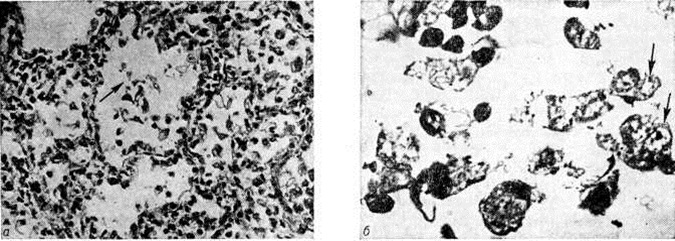

Для Пневмония при острых вирусных респираторных инфекциях (гриппе, парагриппе, респираторно-синцитиальной и аденовирусной) наиболее характерно поражение эпителия слизистой оболочки дыхательных путей и альвеолоцитов. В результате внутриклеточного размножения вирусов происходит повреждение этих клеток с развитием дистрофических и некротических изменений. При благоприятном течении заболевания через несколько дней в них возникают реактивные изменения в виде уплотнения цитоплазмы вокруг участка повреждения — фуксинофильные включения) (рисунок 3, б). Наряду с этим наблюдаются умеренно выраженные воспалительные изменения слизистой оболочки дыхательных путей с преобладанием нарушений кровообращения в виде полнокровия сосудов, выпотевания серозной жидкости в просвет альвеол и небольших кровоизлияний. Отмечаются также небольшие скопления нейтрофильных лейкоцитов и альвеолярных макрофагов. В результате нарушения образования сурфактанта (смотри полный свод знаний) возникают небольшие ателектазы (смотри полный свод знаний), большей частью неполные,— дистелектазы (рисунок 3, в), что особенно выражено у детей раннего возраста, а также компенсаторное очаговое расширение альвеол в других участках лёгких. Макроскопические изменения при этом незначительны и заключаются в основном в катаральном воспалении дыхательных путей и образовании в лёгких небольших участков уплотнения темно-красного или синюшного цвета. Наиболее характерной чертой вирусной Пневмония является гигантоклеточное превращение поражённых эпителиоцитов.

При гриппе поражённые клетки несколько увеличиваются в объёме, в случае же отторжения превращаются в крупные одноядерные клетки, значительно превышающие по размерам обычные альвеолярные макрофаги (рисунок 3, г). Для парагриппа типичны подушкообразные разрастания, сосочковидные выросты слизистой оболочки. При респираторно-синцитиальной инфекции они ещё более выражены. При аденовирусной Пневмония происходит образование крупных одноядерных клеток (гигантоклеточный метаморфоз альвеолоцитов), а также выраженное накопление экссудата (рисунок 3, д). При выздоровлении происходит регенерация эпителия дыхательных путей. Вначале выявляются недифференцированные уплощённые эпителиальные клетки, располагающиеся обычно в несколько рядов (рисунок 3, е), которые в дальнейшем дифференцируются .

Изменения, сходные с морфологический изменениями при вирусной Пневмония, наблюдаются при микоплазменной Пневмония — респираторном микоплазмозе (смотри полный свод знаний Микоплазменные инфекции). Для неё также типично внутриклеточное размножение возбудителя (рисунок 4), хотя возможно и внеклеточное. Поражения носят характер десквамативной Пневмония при весьма умеренных макроскопических изменениях (цветной рисунок 3—5; 6—10).